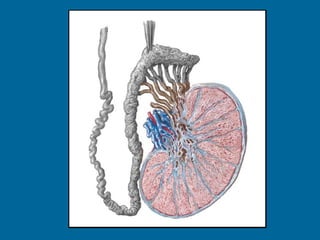

Estructura interna Túnica albugínea - Capsula fibrosa blanca. - Múltiples septos finos convergentes. -  Mediastino testicular  (sector posterior). -  Lóbulos  (entre 250 y 400). Túbulos seminíferos  (840 por testículo). Túbulos rectos  (20 a 30 por testículo).  Rete testis  (a nivel del mediastino). Conductos eferentes  (10 a 15 por testículo).

Estructura interna Túnicaalbugínea - Capsula fibrosa blanca. - Múltiples septos finos convergentes. - Mediastino testicular (sector posterior). - Lóbulos (entre 250 y 400). Túbulos seminíferos (840 por testículo). Túbulos rectos (20 a 30 por testículo). Rete testis (a nivel del mediastino). Conductos eferentes (10 a 15 por testículo).